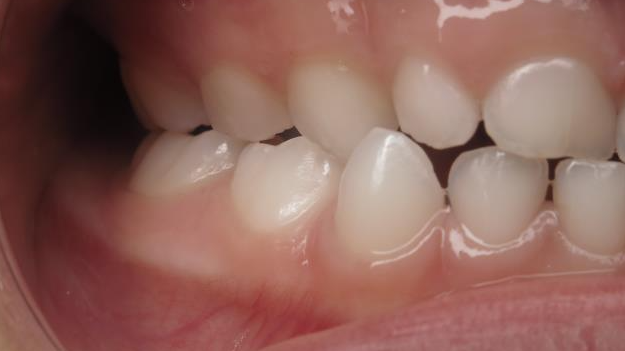

25. bout à bout anterieur 6 ans

dents du haut bout à bout par rapport à celle du bas